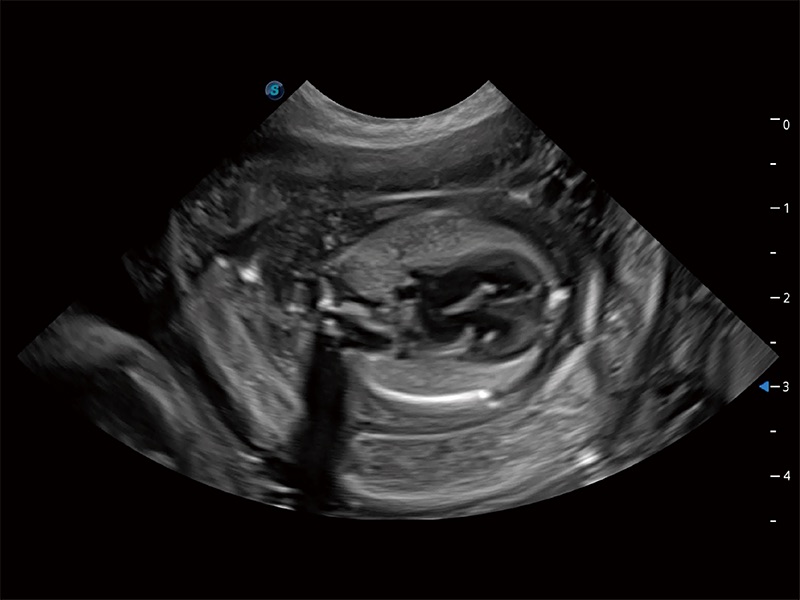

ProPet 80 配备了丰富的心脏探头群、先进的成像技术和专业的心脏测量工具,可帮助动物医生为不同体型和生理结构的动物提供心脏和心肌功能的全面评估。

实时用颜色表示心肌组织运动,观察和定量组织的运动情況,对快速检测与评估心肌的灌注和活性、电传导及心肌收缩和舒张功能等均能提供重要的诊断信息。